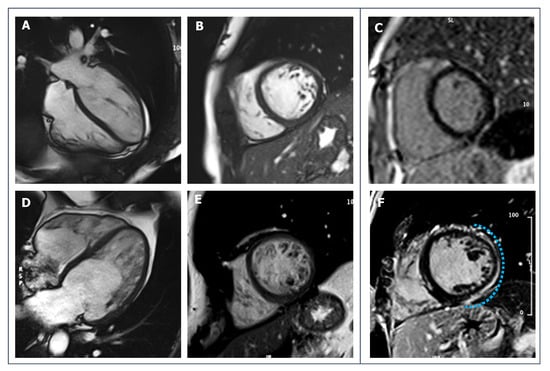

- Corrado, D.; Perazzolo Marra, M.; Zorzi, A.; Beffagna, G.; Cipriani, A.; Lazzari, M.; Migliore, F.; Pilichou, K.; Rampazzo, A.; Rigato, I.; et al. Diagnosis of arrhythmogenic cardiomyopathy: The Padua criteria. Int. J. Cardiol. 2020, 319, 106–114. [Google Scholar] [CrossRef]

- Marcus, F.I.; McKenna, W.J.; Sherrill, D.; Basso, C.; Bauce, B.; Bluemke, D.A.; Calkins, H.; Corrado, D.; Cox, M.G.; Daubert, J.P.; et al. Diagnosis of arrhythmogenic right ventricular cardiomyopathy/Dysplasia: Proposed modification of the task force criteria. Circulation 2010, 121, 1533–1541. [Google Scholar] [CrossRef]

- Cipriani, A.; Bauce, B.; De Lazzari, M.; Rigato, I.; Bariani, R.; Meneghin, S.; Pilichou, K.; Motta, R.; Aliberti, C.; Thiene, G.; et al. Arrhythmogenic right ventricular cardiomyopathy: Characterization of left ventricular phenotype and differential diagnosis with dilated cardiomyopathy. J. Am. Heart Assoc. 2020, 9, e014628. [Google Scholar] [CrossRef]

- Cipriani, A.; Mattesi, G.; Bariani, R.; Cecere, A.; Martini, N.; De Michieli, L.; Da Pozzo, S.; Corradin, S.; De Conti, G.; Zorzi, A.; et al. Cardiac magnetic resonance imaging of arrhythmogenic cardiomyopathy: Evolving diagnostic perspectives. Eur. Radiol. 2022, 32, 1–13. [Google Scholar] [CrossRef]

- Aquaro, G.D.; Barison, A.; Todiere, G.; Grigoratos, C.; Ali, L.A.; Di Bella, G.; Emdin, M.; Festa, P. Usefulness of combined functional assessment by cardiac magnetic resonance and tissue characterization versus task force criteria for diagnosis of arrhythmogenic right ventricular cardiomyopathy. Am. J. Cardiol. 2016, 118, 1730–1736. [Google Scholar] [CrossRef]

- Czimbalmos, C.; Csecs, I.; Dohy, Z.; Toth, A.; Suhai, F.I.; Müssigbrodt, A.; Kiss, O.; Geller, L.; Merkely, B.; Vago, H. Cardiac magnetic resonance based deformation imaging: Role of feature tracking in athletes with suspected arrhythmogenic right ventricular cardiomyopathy. Int. J. Cardiovasc. Imaging 2019, 35, 529–538. [Google Scholar] [CrossRef]